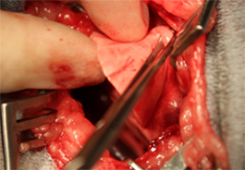

病名:肝細胞癌 手術法:内側右葉完全肝葉切除術

症例:11歳 避妊雌 MiX犬 12kg

主訴:1週間前から食欲の低下と嘔吐で来院されました。

検査:腹部超音波検査にて肝臓内側右葉に直径約12cm大の肝臓腫瘍が認められました。また、胆のうに重度の胆泥の貯留を認めました。

治療:飼い主様の希望により、肝臓腫瘍摘出手術と胆嚢切除手術行いました。肝臓腫瘍摘出は特に血管系の処理が重要で基本的な結紮技術はもちろん、超音波乳化吸引装置や血管シーリング装置などを駆使し血管を一つずつ処理して行きます。

肝臓腫瘍と胆嚢を摘出した写真です。肝臓腫瘍摘出には超音波乳化吸引装置を使用し、かなり安全に手術が可能でした。

胆嚢内にはゼリー状の内容物が詰まっていました。手術後は2日後から食欲も改善し、状態も改善しました。病理検査で肝細胞癌との診断でしたが、手術で切除しきれているとのことで、今後は無治療で経過観察中です。